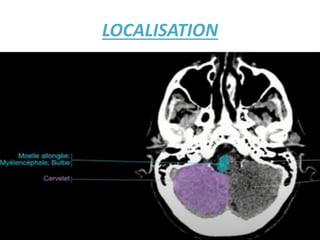

LOCALISATION

IL FAUT DETERMINER L'ÉTAGE Où VOUS ETES SUR LA TDM

POUR PRECISER LA LESION : Lésions intracrâniennes sus- et

sous-tentorielles !!

• L'intérieur du crâne est divisé en deux étages par la tente

du cervelet:

• L'étage sus-tentoriel qui contient les hémisphères

cérébraux et les structures profondes situées autour du

IIIéme ventricule.

• L'étage sous-tentoriel (que l'on pourrait aussi appeler

«fosse postérieure») qui contient le cervelet et le tronc

cérébral. Cet espace est limité supérieurement par la tente

du cervelet, inférieurement par le trou occipital et

latéralement par la boite crânienne.